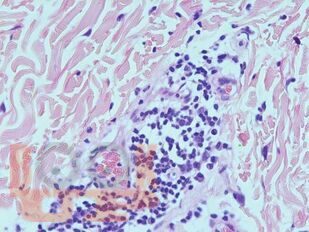

Атлас содержит авторские гистологические иллюстрации различных ревматических заболеваний, включая ревматоидный артрит, системную красную волчанку, системную склеродермию, а также редкие патологии: склеромикседему, IgG4‑ассоциированное заболевание, панникулиты, аутовоспалительный синдром, ассоциированный с адъювантами (ASIA‑синдром). Широко представлены системные васкулиты (болезнь Такаясу, гигантоклеточный артериит, узелковый полиартериит, гранулематоз с полиангиитом, эозинофильный гранулематоз с полиангиитом и др.). Гистологические препараты сопровождаются фотографиями пациентов.